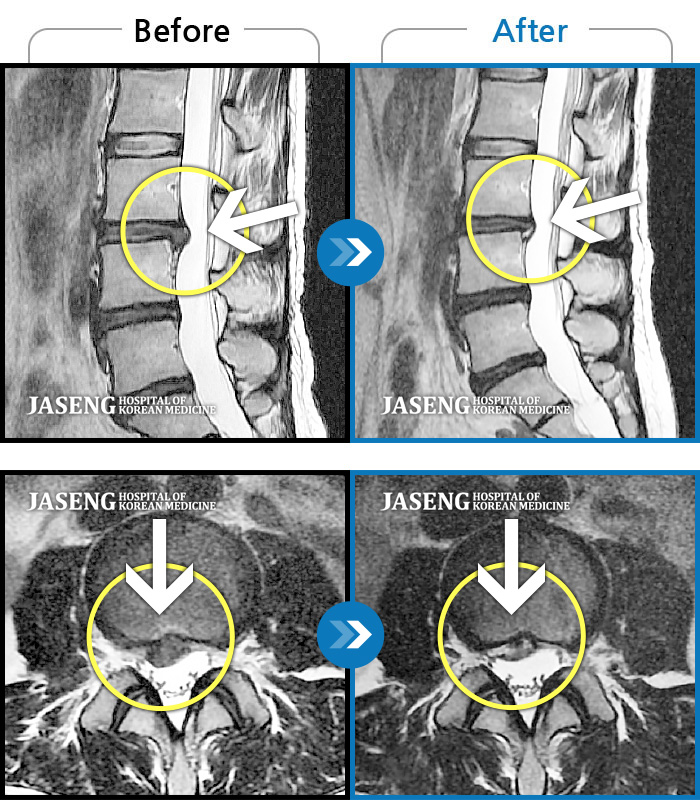

MRI 치료사례

짐을 들면서 정리하다가 디스크가 터져서 내원, 후에 통증이 더 심해져 내원